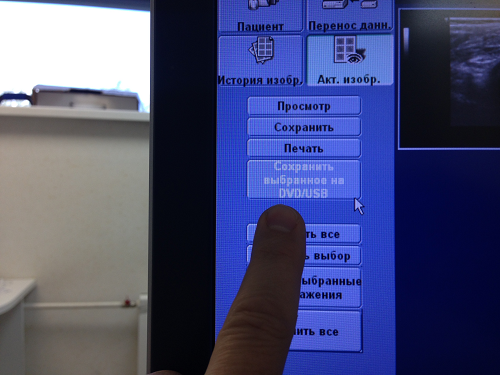

Как вы видите один из файлов на который указывает мой палец пока не выбран. Пока он не выбран машина с ним работать не будет.

Выбор файла, нескольких файлов, отмена выбора, возможность затереть и перенести на носитель определяется на этом экране чередой экранных кнопок с надписями в по левому краю экрана. Получив доступ к этому экрану прочитайте надписи на этих кнопках все...

В данном случае мой палец указывает на "Запись на CD\DVD\USB.

Как вы видите один из файлов на который указывает мой палец пока не выбран. Пока он не выбран машина с ним работать не будет.

Выбор файла, нескольких файлов, отмена выбора, возможность затереть и перенести на носитель определяется на этом экране чередой экранных кнопок с надписями в по левому краю экрана. Получив доступ к этому экрану прочитайте надписи на этих кнопках все...

В данном случае мой палец указывает на "Запись на CD\DVD\USB.